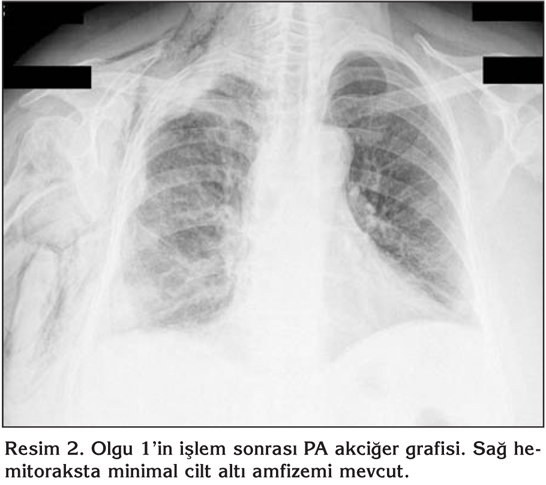

Bilinen hipertansiyon d???nda rahats?zl??? olmayan hastan?n bir ay ?nce ba?layan ?ks?r?k ve nefes darl???, sa? yan a?r?s? ?ikayetleri mevcutmu?. Sa? plevral ef?zyonu saptanan hastaya uygulanan torasentez sonras? eks?da vasf?nda plevral mayii elde edilmi?. Sistemik muayenesinde sa? akci?er alan?nda solunum seslerinin al?namamas? ve ayn? alanda perk?syonla matite al?nmas? d???nda bulgu saptanmad?. Vital bulgular? normal s?n?rlar i?indeydi. Toraks bilgisayarl? tomografi (BT) incelemesinde mediastinal yap?lar k?smen sola deviye, sa? ?st ve alt paratrakeal lokalizasyonlarda en b?y??? 23 mm ?ap?nda multip lenfadenomegaliler izlenmekteydi. Sol alt paratrakeal ve subkarinal lokalizasyonlarda da ?ap? 1 cm civar?nda lenfadenomegaliler mevcuttu. Sa? hemitoraksta masif plevral ef?zyon izlenmekteydi ve sa? akci?er tamamen atelektazikti. Resim 1 ve 2'de olgunun s?ras?yla i?lem ?ncesi ve sonras? PA akci?er grafileri g?r?lmektedir.

Resim 1

Resim 2

Hastan?n plevra s?v?s? eks?da karakterinde ve lenfosit hakimiyetinde saptand?. Terap?tik torasentez yap?ld?. Hastaya tan?sal ama?l? semirijid torakoskopi yap?ld?. Pariyetal plevra ?zerindeki nod?llerden yeterli say?da biyopsi ?rnekleri al?nd?. Hastada i?lem sonras? hafif cilt alt? amfizemi d???nda herhangi bir komplikasyon g?zlenmedi. Ertesi g?n t?p torakostomisi sonland?r?ld?. Al?nan biyopsi sonucu imm?nhistokimyasal ?al??mada t?m?r h?creleri TTF-1 (pozitif), CEA (pozitif), Ber Ep 4 (negatif), Sitokeratin 7 (pozitif), Sitokeratin 20 (negatif), Mezotelin (pozitif), Kalretinin (negatif) imm?nreaktivite g?sterdi ve akci?er k?kenli adenokarsinom ile uyumlu olarak saptand?.